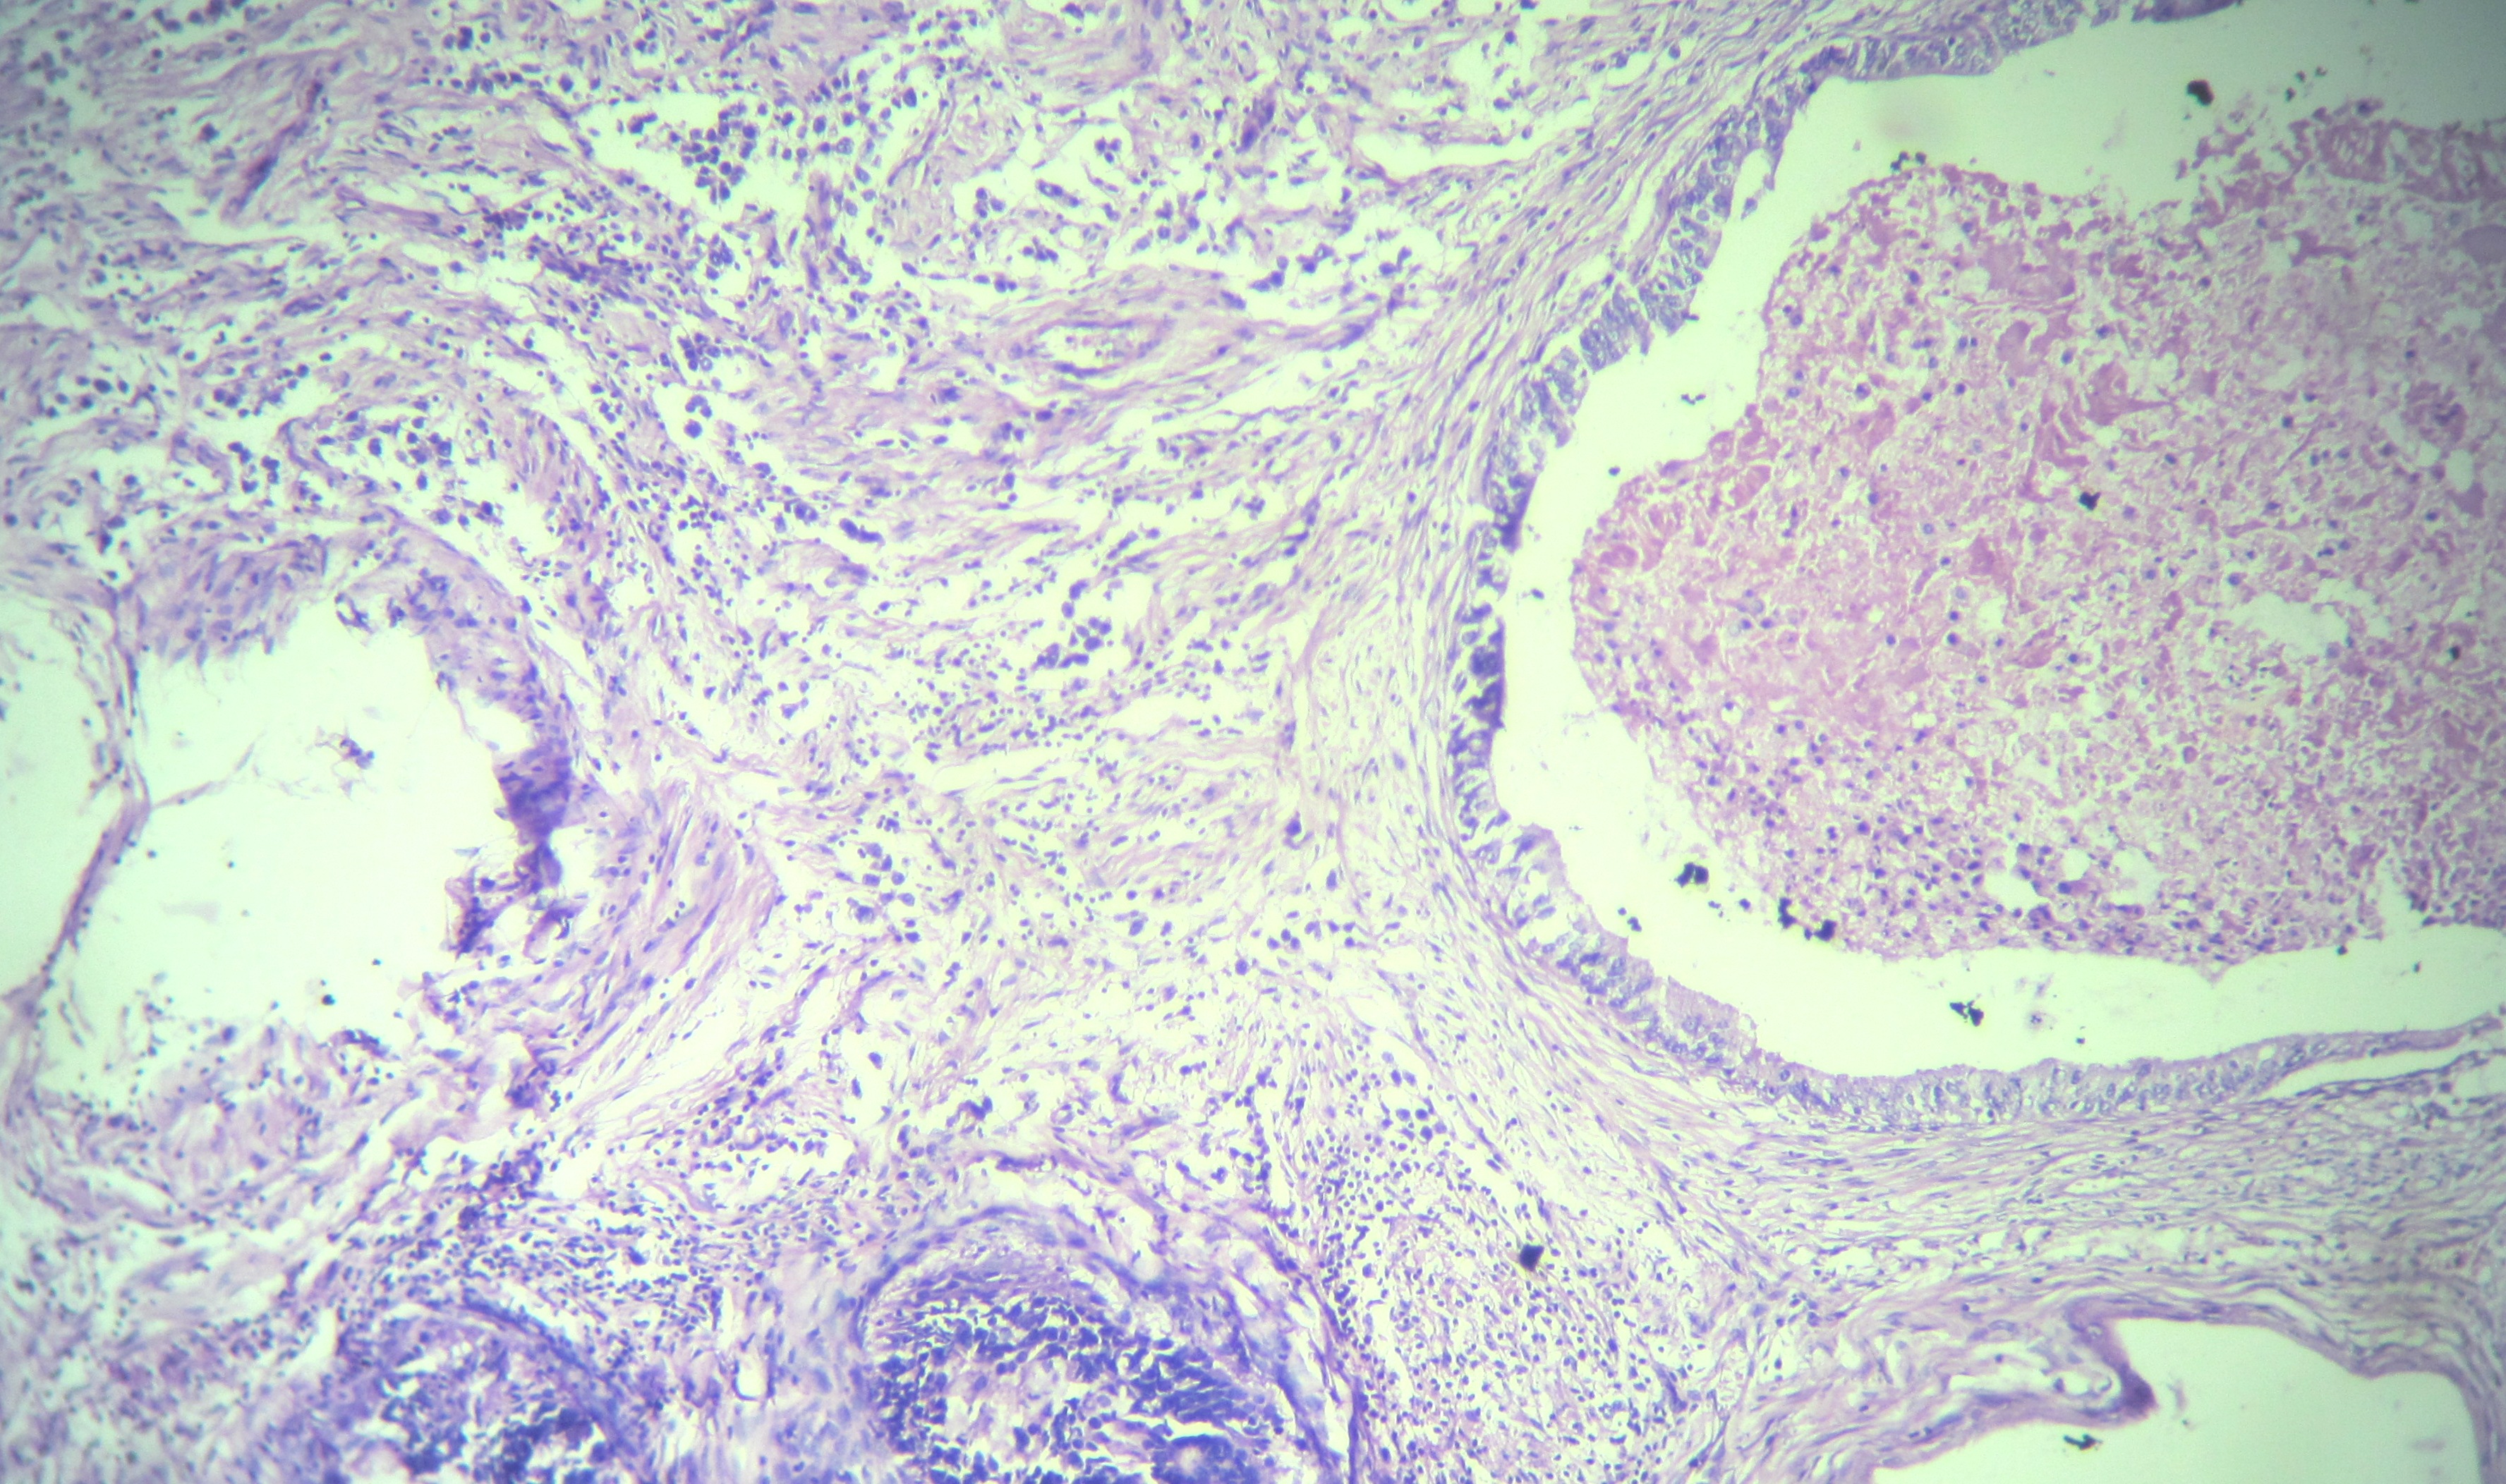

Collision tumors of ovary are rare neoplasms and most commonly consist of a teratoma with mucinous tumor. Combination of papillary serous cystadenocarcinoma and dysgerminoma was yet to be reported. A twenty years female patient presented with a large tumor of right ovary. Microscopically it was diagnosed as a collision tumor of ovary composed of dysgerminoma and serous cystadenocarcinoma. Mixed tumour can arise from divergent differentiation of a single type of stem cell. But components of collision tumor must arise from separate clones. Possibility of collision tumour should always kept in mind during assessment of difficult ovarian tumors to avoid diagnostic error.